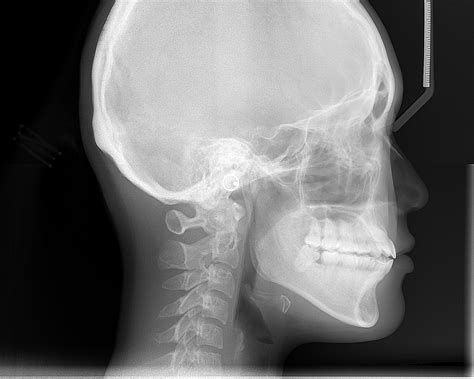

Understanding the intricacies of medical terminology can be daunting, especially when encountering specialized terms like Cephalo. This term, derived from Greek, refers to the head, and it is frequently used in various medical contexts to describe conditions, procedures, and anatomical structures related to the head and brain. This blog post delves into the significance of the Cephalo medical term, its applications, and its relevance in modern medicine.

The term Cephalo is rooted in the Greek word "kephalē," which means head. In medical terminology, it is often used as a prefix to describe conditions, procedures, or anatomical features related to the head. For instance, Cephalohematoma is a condition where blood collects between the skull and the periosteum, the membrane covering the bone. This condition is commonly seen in newborns after a difficult delivery.

The Cephalic Index is a measurement used to describe the shape of the human skull. It is calculated by dividing the maximum width of the skull by its maximum length and then multiplying by 100. This index helps in classifying skull shapes into different categories, such as dolichocephalic (long and narrow), mesocephalic (moderately broad), and brachycephalic (broad and short).

• X-ray: Used to assess bone structures and identify fractures or deformities.